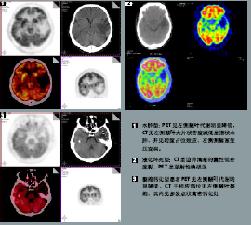

其它輔助檢查:1.腦電圖節律減慢至8~9Hz以下,雙側額區、顳區和中央區出現瀰漫性θ波可伴局灶性陣發高波幅δ節律視覺誘發電位(VEP)腦幹聽覺誘發電位(BAEP)和事件相關電位(ERP)P300的潛伏期均較同齡對照組明顯延長40%的患者不能誘發明顯的P300波形提示認知功能嚴重損害;2.影像學檢查CT可見腦皮質輕度萎縮,不同程度的腦室擴張,雙側腦室前角、后角及體部兩側出現邊界模糊的斑片狀低密度影可伴基底核、丘腦及腦橋等穿髓小動脈豐富區多發性腔隙性梗死。MRI檢查可見腦萎縮以白質為主,皮質較輕,雙側腦室周圍及半卵圓中心散在多發的T1WI低信號T2WI高信號伴多發腔隙性梗死灶PET檢查顯示雙側腦室周圍白質腦血流瀰漫性減少葡萄糖和氧代謝顯著降低。治療